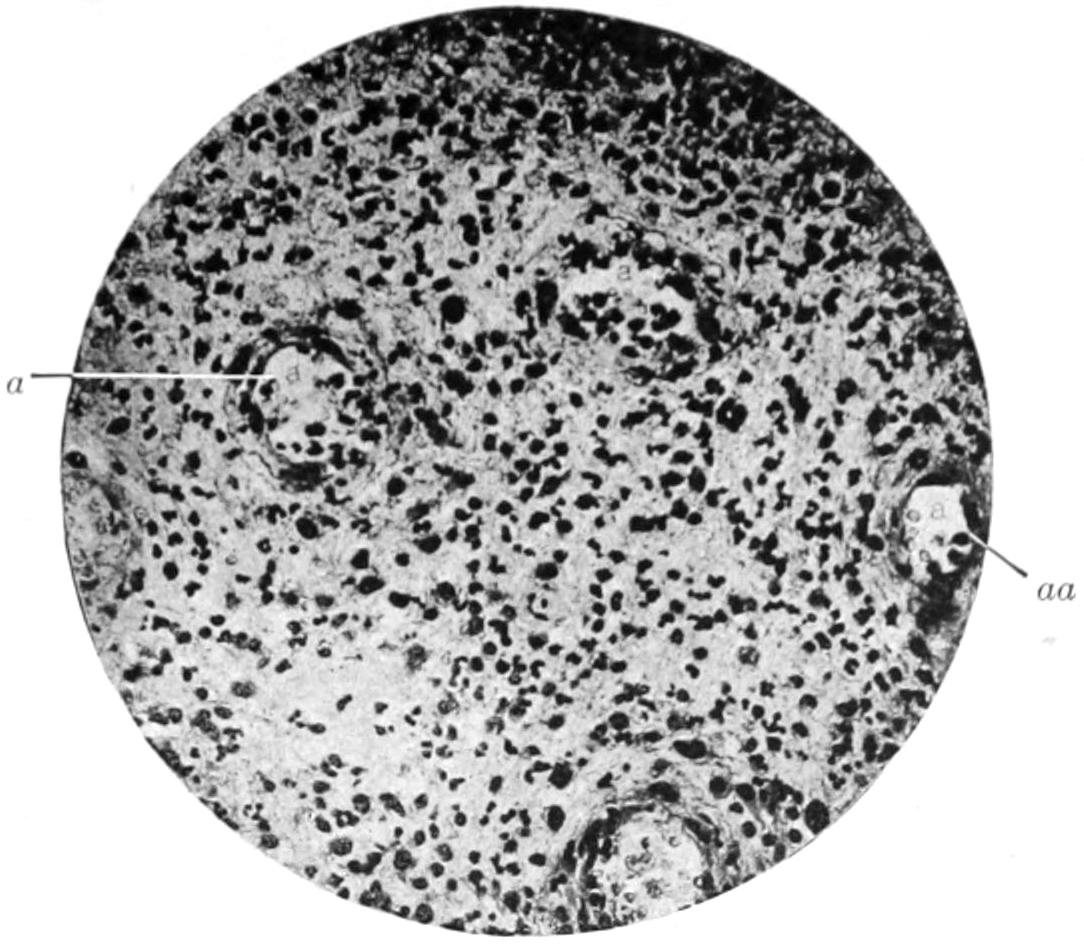

PLATE I

Fig. I.

Fig. II.

Fig. III.

Fig. IV.

Fig. V.

Fig. VI.

Fig. VII.

Fig. VIII.

DRAWN BY J. N. Z. CHASE

PLATE I.

BLOOD.

(Ehrlich triple stain.)

(Prepared by Dr. I. P. Lyon.)

Fig. I. TYPES OF LEUCOCYTES.

a. Polymorphonuclear Neutrophile. b. Polymorphonuclear Eosinophile. c. Myelocyte (Neutrophilic). d. Eosinophilic Myelocyte. e. Large Lymphocyte (large Mononuclear). f. Small Lymphocyte (small Mononuclear).

Fig. II. NORMAL BLOOD.

Field contains one neutrophile. Reds are normal.

Fig. III. ANÆMIA, POST-OPERATIVE (secondary).

The reds are fewer than normal, and are deficient in hæmoglobin and somewhat irregular in form. One normoblast is seen in the field, and two neutrophiles and one small lymphocyte, showing a marked post-hæmorrhagic anæmia, with leucocytosis.

Fig. IV. LEUCOCYTOSIS, INFLAMMATORY.

The reds are normal. A marked leucocytosis is shown, with five neutrophiles and one small lymphocyte. This illustration may also serve the purpose of showing the leucocytosis of malignant tumor.

Fig. V. TRICHINOSIS.

A marked leucocytosis is shown, consisting of an eosinophilia.

Fig. VI. LYMPHATIC LEUKÆMIA.

Slight anæmia. A large relative and absolute increase of the lymphocytes (chiefly the small lymphocytes) is shown.

Fig. VII. SPLENO-MYELOGENOUS LEUKÆMIA.

The reds show a secondary anæmia. Two normoblasts are shown. The leucocytosis is massive. Twenty leucocytes are shown, consisting of nine neutrophiles, seven myelocytes, two small lymphocytes, one eosinophile (polymorphonuclear) and one eosinophilic myelocyte. Note the polymorphous condition of the leucocytes, i. e., their variations from the typical in size and form.

Fig. VIII. VARIETIES OF RED CORPUSCLES.

a. Normal Red Corpuscle (normocyte). b, c. Anæmic Red Corpuscles. d-g. Poikilocytes. h. Microcyte. i. Megalocyte. j-n. Nucleated Red Corpuscles. j, k. Normoblasts. l. Microblast. m, n. Megaloblasts.

The value of a careful blood examination is well illustrated by Plate I, prepared by Dr. Irving P. Lyon, in which are displayed the alterations of greatest interest to the surgeon.